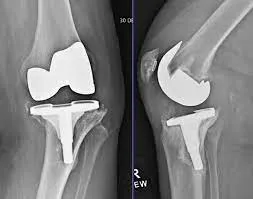

Failed Joint Surgeries

Correcting complications or unsatisfactory outcomes from earlier joint replacement procedures.